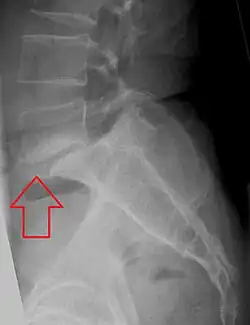

Spondylolisthesis

Spondylolisthesis is een rugaandoening waarbij de verbinding tussen twee wervels zodanig is verslapt of afwezig is dat de wervels zijn verschoven ten opzichte van elkaar, meestal op basis van een spondylolyse.